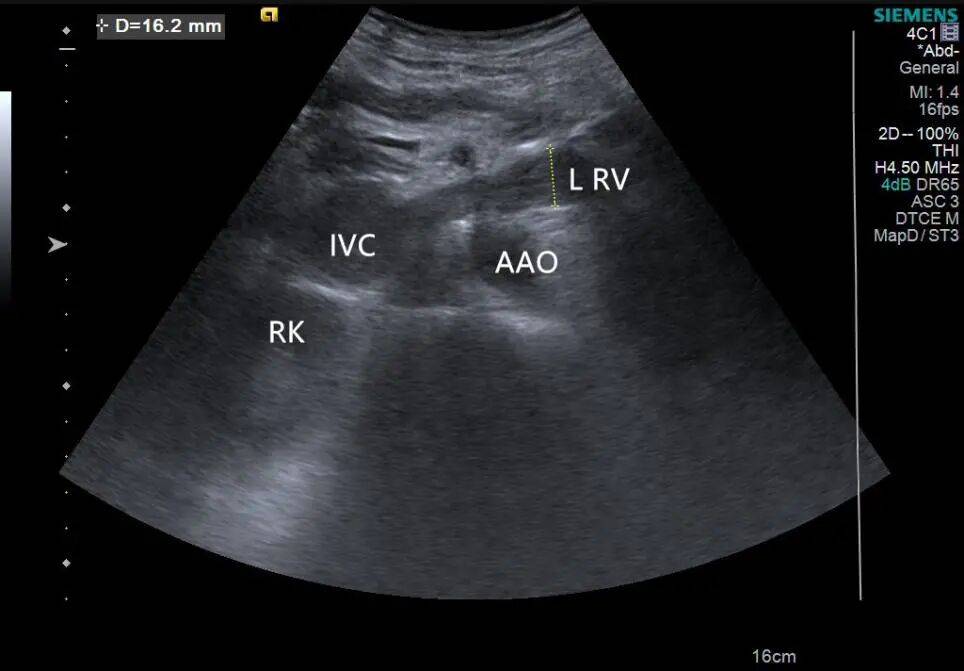

2. 左肾静脉增宽,前后径约 16 mm,其内充满低回声,下腔静脉增宽,前后径约 29 mm,其内充满低回声,向上延伸至右心房入口处。CDFI:左肾静脉、下腔静脉及其内低回声见星点状血流信号(图 3、4)。

图 3 灰阶超声示肾静脉及下腔静脉癌栓超声表现( RK 右肾 IVC 下腔静脉 L RV 左肾静脉 AAO 腹主动脉)